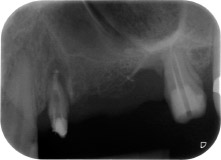

Un mois plus tard, le jour de l'intervention, la douleur et l'inflammation sur la dent 24 étaient minimes mais une mobilité de classe 2 de Miller était toujours observable. Après ouverture des lambeaux et nettoyage des tissus périapicaux et périradiculaires infectés, l'étendue du défaut osseux est devenue parfaitement visible (Figures 2 et 3).

À la racine de la dent, il manquait la totalité de l'os vestibulaire et distal. L'attache était essentiellement limitée à la racine palatine, venant ainsi confirmer le pronostic défavorable initial. La dent 27 présentait également une attache horizontale réduite et une raréfaction apicale minime (cf. Fig. 1), sans symptômes cliniques.